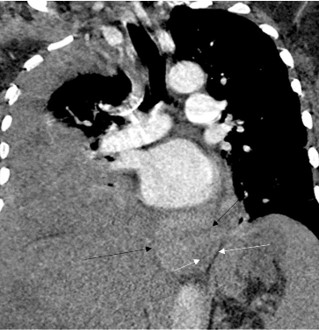

CT angiogram of the chest was negative for a pulmonary embolism or pneumonia. Abdominal CT demonstrated a cirrhotic appearing liver with mild ascites, paraesophageal varices, and recanalization of the umbilical vein consistent with collateral venous flow in the setting of portal hypertension (Figure 1).

Figure 1: Contrast Enhanced CT chest, abdomen and pelvis on admission: Coronal image showing cirrhotic liver, ascites and paraesophageal collaterals (arrow). Also visualized are spleno-renal collaterals (arrow head).